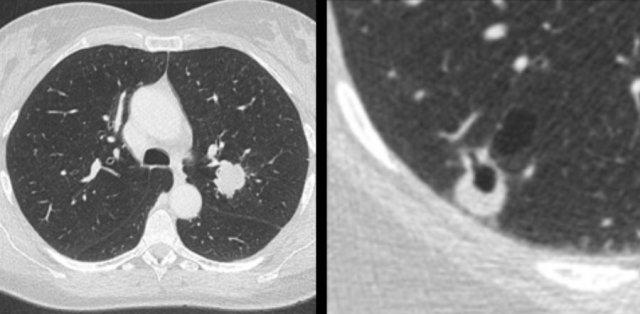

Các hình ảnh minh họa một ví dụ khác về ung thư phổi dạng nang biểu hiện quá trình ‘đặc hóa’.

Đặc hóa là quá trình ngược lại với tạo hang.

Đặc hóa là một quá trình thường gặp trong ung thư phổi dạng nang – trong đó thành phần mô đặc tăng dần theo thời gian và cuối cùng có thể lấp đầy hoàn toàn các khoang kính mờ và/hoặc khoang khí dạng nang trước đó, dẫn đến hình thành một khối đặc.

Đây là một ví dụ khác về ung thư phổi dạng nang biểu hiện quá trình ‘đặc hóa’, từ tổn thương tiền thân ban đầu với dày thành không đều kín đáo tiến triển thành một khối đặc tại thời điểm chẩn đoán.